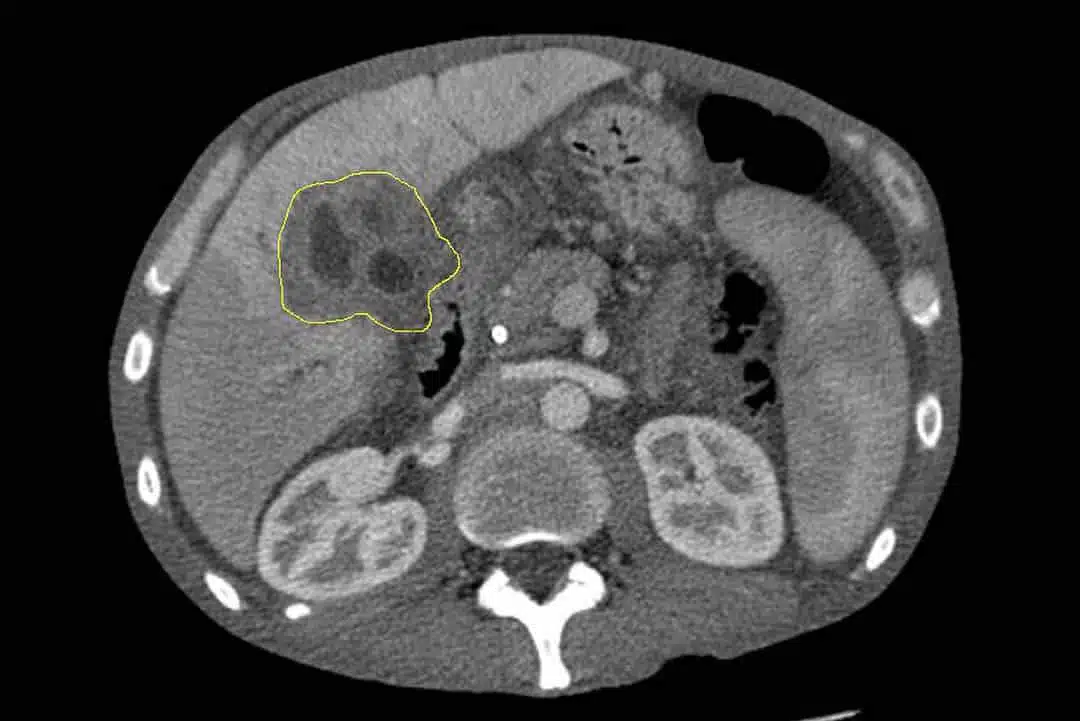

Quelques mois plus tard, un autre signe apparaît : des douleurs abdominales. Comme beaucoup, elle pense à une simple intoxication alimentaire ou à un trouble digestif passager. Cependant, ces douleurs persistent. Après plusieurs consultations, on lui diagnostique initialement des calculs biliaires et un stent est inséré dans son canal biliaire. Ce n’est que plus tard qu’une lésion hépatique est découverte. Malheureusement, il était déjà trop tard.

Ce n’est qu’en janvier 2024 que Sian reçoit la terrible nouvelle : elle est atteinte d’un cholangiocarcinome, un cancer des voies biliaires, à un stade avancé. Son pronostic est sans espoir : il ne lui reste que peu de temps à vivre. Malgré tout, seulement 18 jours plus tard, elle s’éteint.